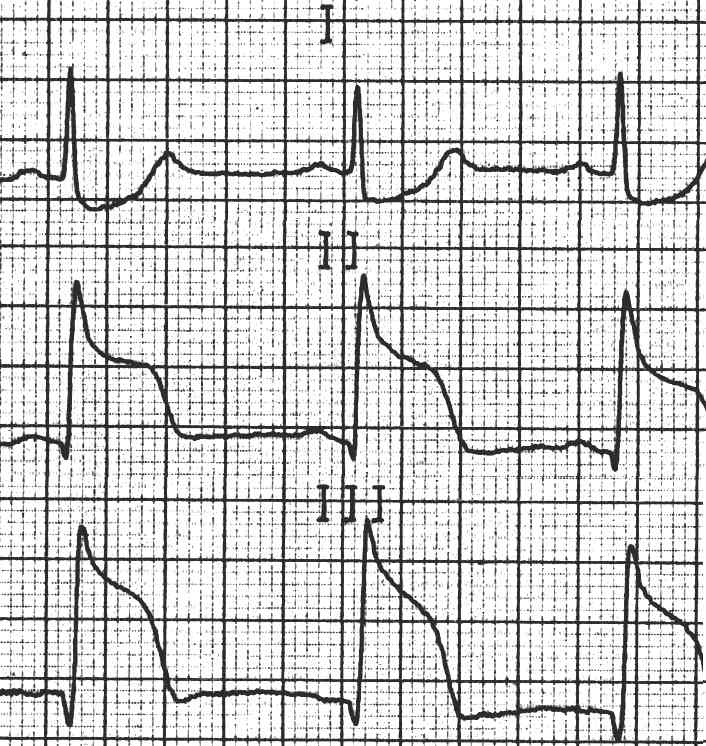

Quiz 6: Akuter infero - posteriorer Myocardinfarkt

43 - jähriger DB-Angestellter, seit zwei Tagen thorakale Missempfindungen „wegen Ozon“, seit 1 h massiver retrosternaler Schmerz und kalter Schweiss.

Verlauf unter systemischer Thrombolyse mit Streptokinase.